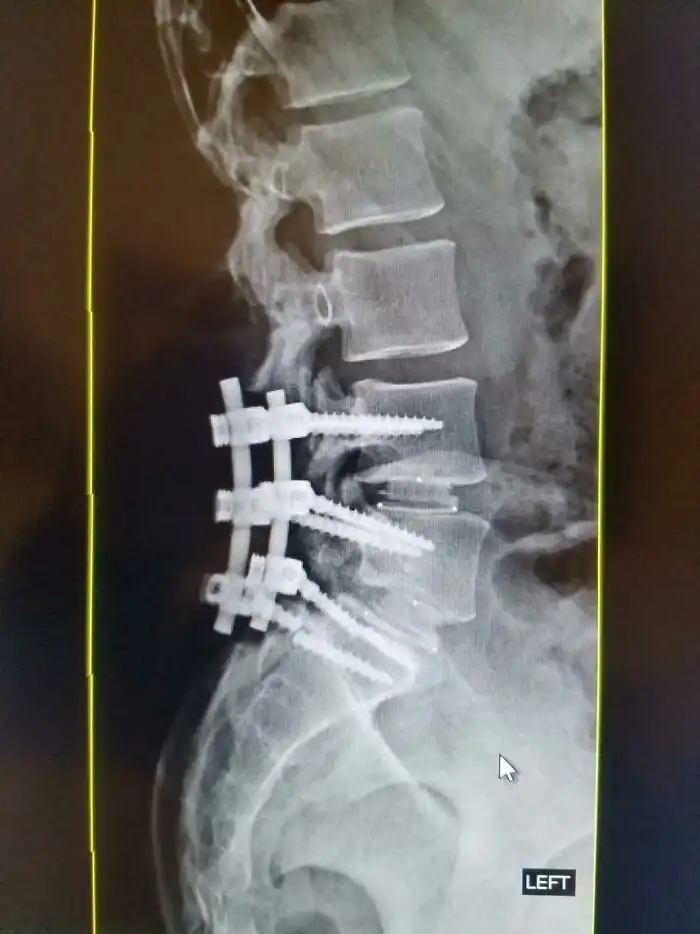

33. "Тот самый случай, когда я сломал один из винтов в спине"